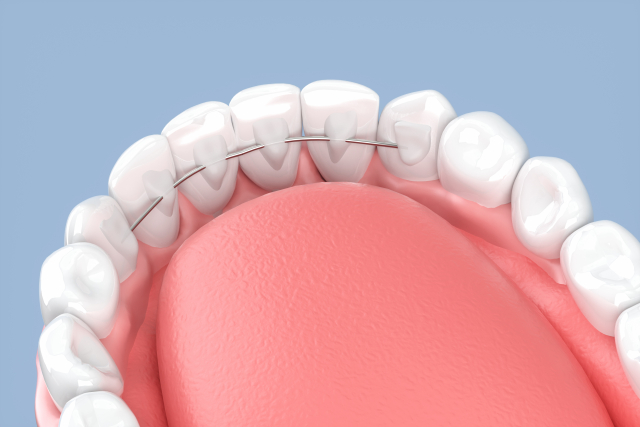

歯列矯正ではワイヤー(ブラケット装置)やマウスピースで力をかけて歯を動かし、歯並びを整えていきます。装置で力をかけて歯を動かすという治療の特性上、歯科矯正によってブラックトライアングルができてしまうことがあるのです。

IPRは、矯正治療の一環として行われる一般的な治療法で、歯と歯の間をわずかに削って調整していく治療法です。「ディスキング」や「ストリッピング」とも呼ばれます。